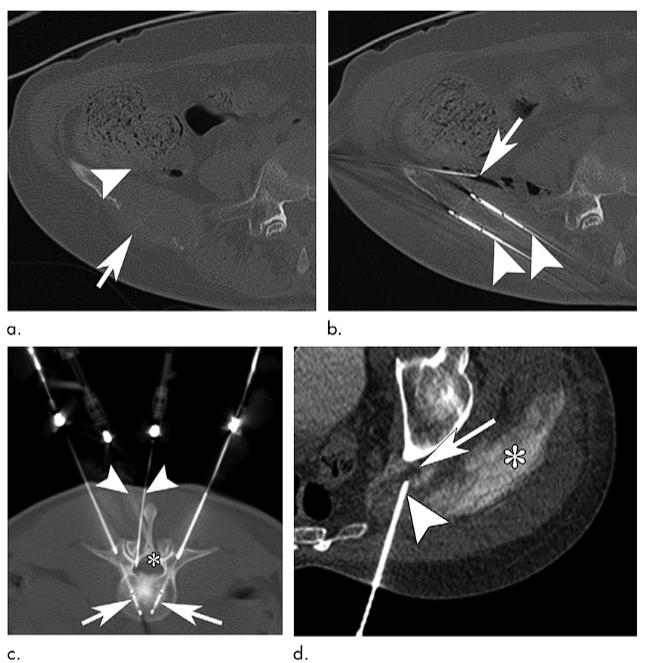

通过-140℃极冷冻结和+45℃快速复温的交替循环,在微创条件下精准杀灭肿瘤细胞,保护周围健康组织。

实时影像监测冰球范围,精确控制治疗区域,最大程度保护正常组织和重要器官